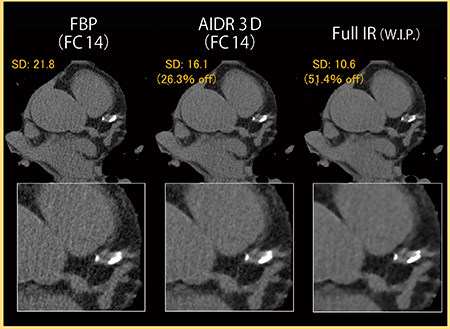

3.心臓

東芝メディカルシステムズでは現在,心電同期に対応したFull IRの開発も進められており,当院にて検討を行った。

図7は,左前下行枝(LAD)起始部の石灰化症例である。FBPやAIDR 3Dでは,石灰化にブルーミングアーチファクトが見られるが,Full IRではほとんど認められず,石灰化の境界も明瞭である。

図8は,陳旧性心筋梗塞症例の冠動脈CTAであるが,Full IRでは血管や臓器の境界がより明瞭である。心尖部には陳旧性の梗塞巣が認められるが,淡い低吸収の梗塞巣の描出能も向上するのではないかと期待している。図9は同一症例のCurved MPR画像であるが,Full IRではノイズ低減に加え,血管や構造物の境界がきわめて明瞭となっている。

図7 カルシウムスコア(2.2mSv)

図8 冠動脈CTA(2.1mSv)

100kV,540mA,0.5mm